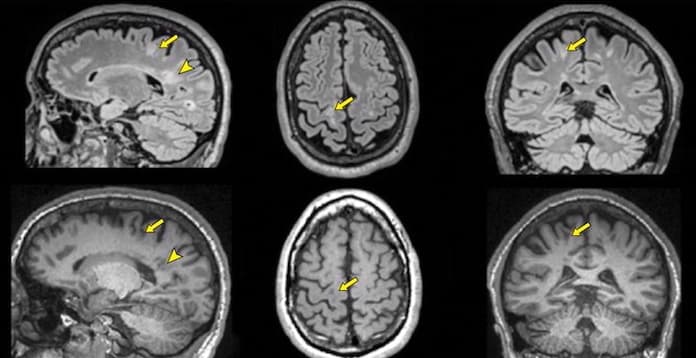

Les QReports, outils essentiels pour le diagnostic et le suivi de la SEP par IRM, ont besoin d’un consensus scientifique pour être utilisés en pratique clinique. Des experts européens de cette pathologie ont été appelés à se prononcer sur les critères d’élaboration de cet outil et des recommandations qui permettront d’affiner et améliorer l’adoption clinique des QReports ont été publiées dans un article de la Revue European Radiology.

Le Syndrome radiologiquement isolé est le premier signe avant-coureur de la SEP en IRM. Ce syndrome est synthétisé dans les Critères de McDonald, qui a fait l’objet d’une mise à jour en 2004 avec de nouvelles implications cliniques et radiologiques. Un article publié dans l’American Journal of Roent...